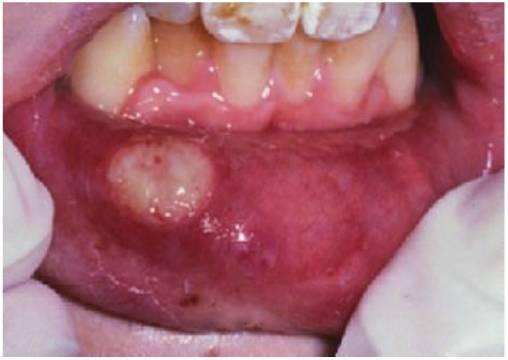

- Aftas mayores (fig. 8.6B).

Las aftas menores suponen la mayoría de los casos y están formadas por dos a cinco úlceras que miden más de 5mm y que se presentan en la mucosa no queratinizada. Existe un esfacelo central amarillo típico con un borde eritematoso. Las úlceras curan en 10-14 días sin dejar cicatriz. No se ha llegado a un acuerdo con respecto a la causa de la UAR. Existen algunas pruebas que indican una base genética del trastorno, con una mayor incidencia de ulceración en niños cuyos progenitores tienen UAR. Algunos estudios indican que la UAR está asociada con deficiencias nutricionales, por lo que son necesarios estudios hematológicos. En las aftas mayores también puede quedar afectada la mucosa queratinizada, lo que deriva en úlceras de mayor tamaño, más duraderas y que curan dejando una cicatriz.